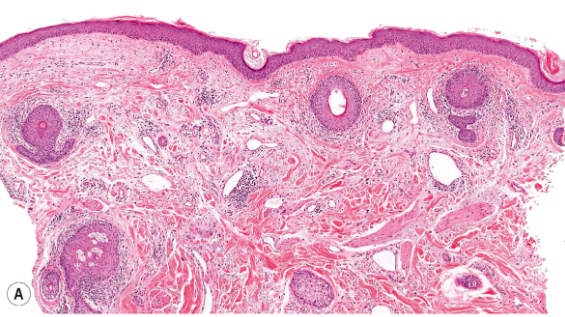

What is this and talk about hwat you see

A

Vascular enlargement

Mild edema

this is Erythematotelangiectatic rosacea